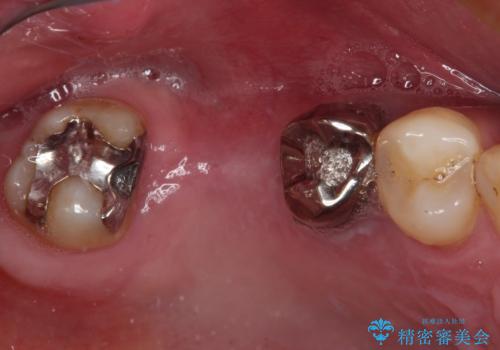

![[ インプラント体・カスタムアバットメント・ジルコニアクラウン ] インプラントの構造の症例 治療前](https://seimitsushinbi.jp/wp/wp-content/uploads/2024/02/d7b3d7509c0cc77833268d7096e1730b-500x350.jpg?v=1708928260)